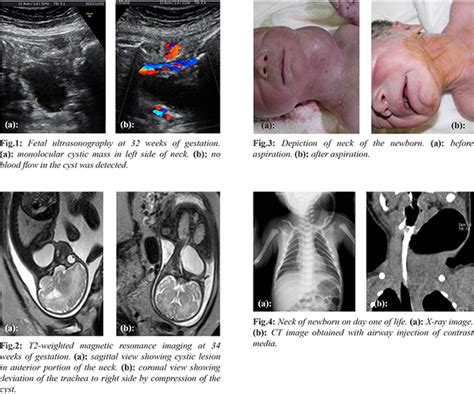

Pyriform Sinus Fistula Presenting as Fetal Cervical Cyst